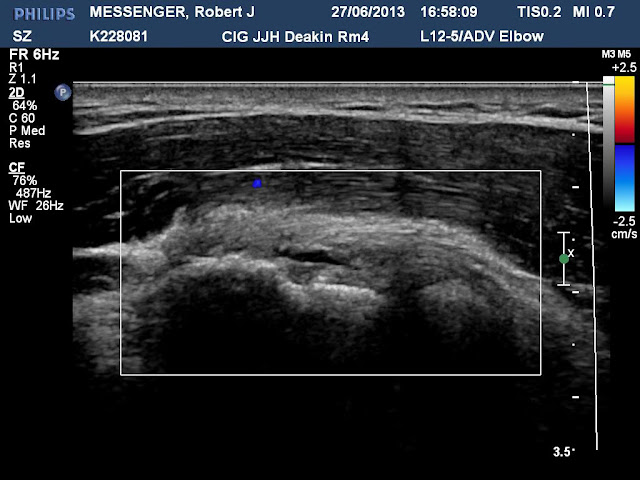

As Wimbledon enters day four and Richard Polt packs for London - though to look at Turners, not tennis - we can reveal a previously unknown malady: Typewriter Elbow*. This is what it looks like:

Technically speaking, it's a "partial thickness intrasubstance tear of the origin of extensor carpi radialis longus [which is] approximately 7mm in length".

This evening I had ultrasound scans done on my Typewriter Elbow by Canberra Imaging at John James Hospital. Contrary to what my doctor and physiotherapist thought, I have torn the muscle. I won't be having a cortisone injection, because while this would ease the pain it would hinder the recovery. The tear isn't long enough to warrant surgery.